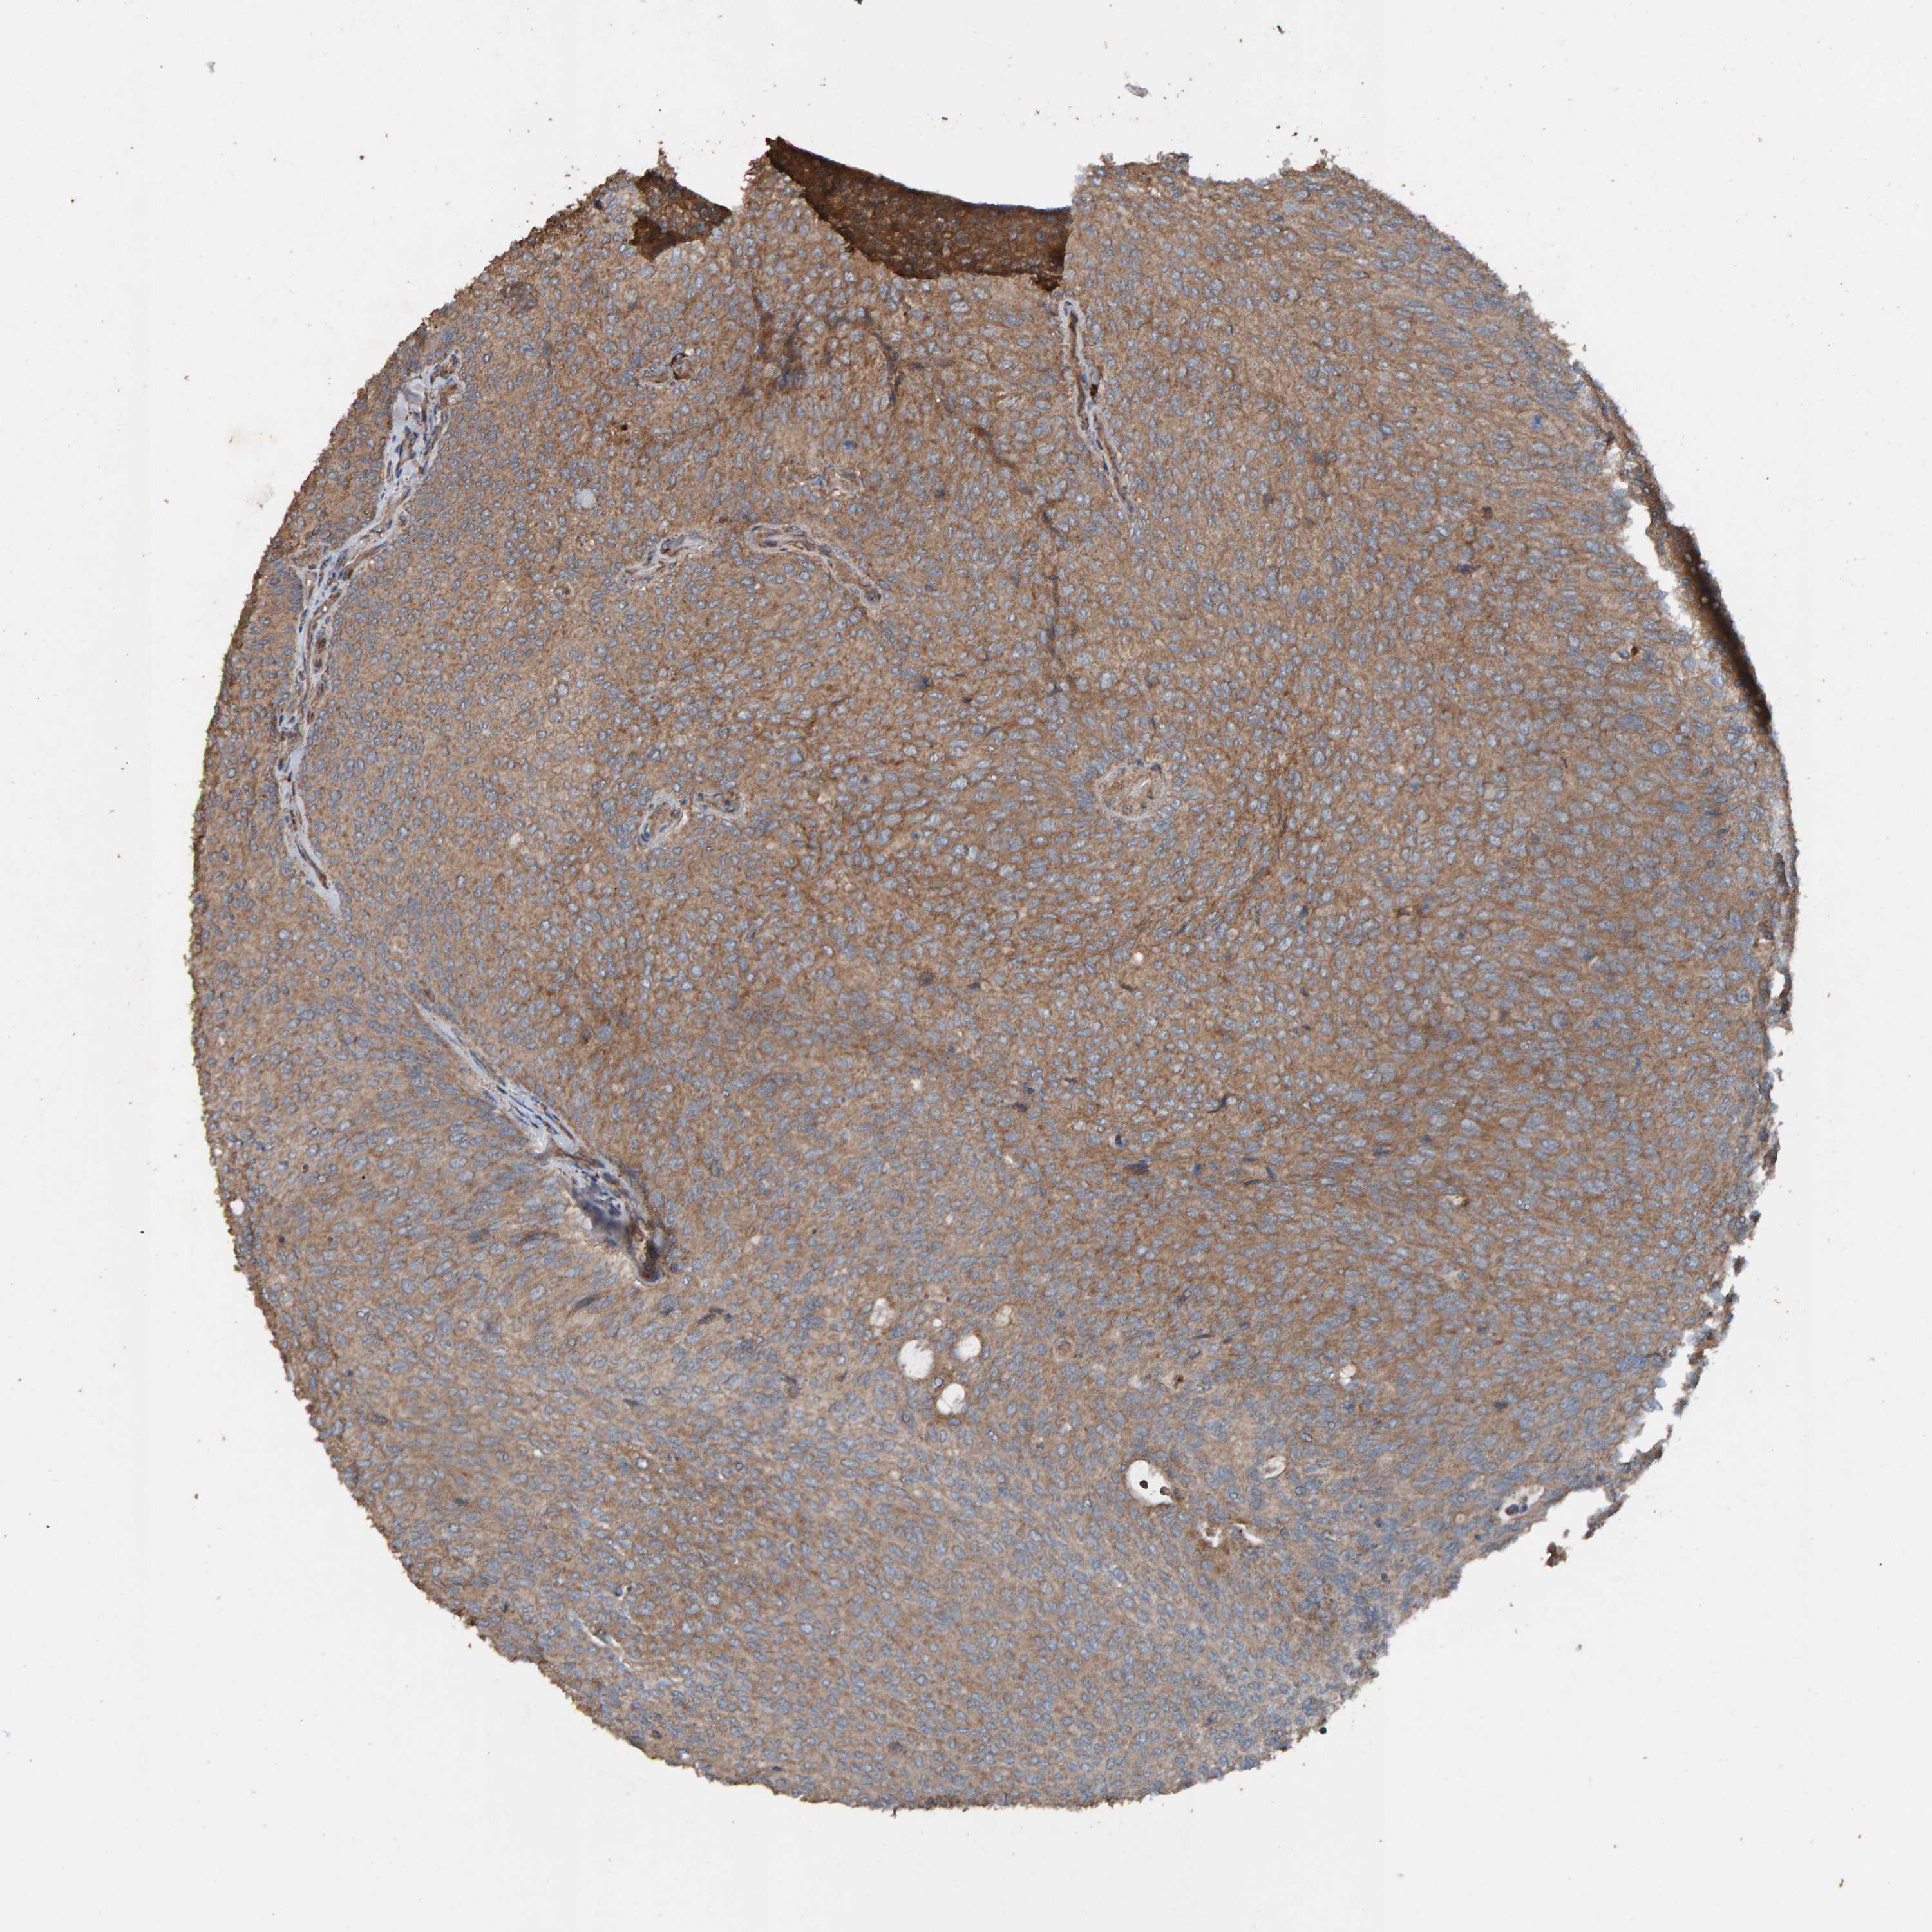

UROTHELIAL CANCER - Protein expressioni

A mouse-over function shows sample information and annotation data. Click on an image to view it in a full screen mode. Samples can be filtered based on level of antibody staining by selecting one or several of the following categories: high, medium, low and not detected. The assay and annotation is described here.

Antibody stainingi

Antibody staining in the annotated cell types in the current human tissue is reported as not detected, low, medium, or high, based on conventional immunohistochemistry profiling in selected tissues. This score is based on the combination of the staining intensity and fraction of stained cells.

Each image is clickable and will lead to virtual microscopy that enables deeper exploration of all samples and also displays staining intensity scores, fraction scores and subcellular localization as well as patient and tissue information for each sample.

Antibody HPA023384

Staining

High

Medium

Low

Not detected

Intensity

Strong

Moderate

Weak

Negative

Quantity

>75%

75%-25%

<25%

None

Location

Urothelial carcinoma, Low grade

Urothelial carcinoma, High grade